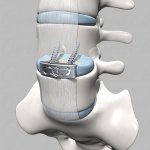

- csípőprotézis műtét, rehabilitáció, szövődmények

- Gyakorlatok utáni rehabilitáció gerinc arthroplasticán?

- Timing utáni felépülés gerinc arthroplasticán